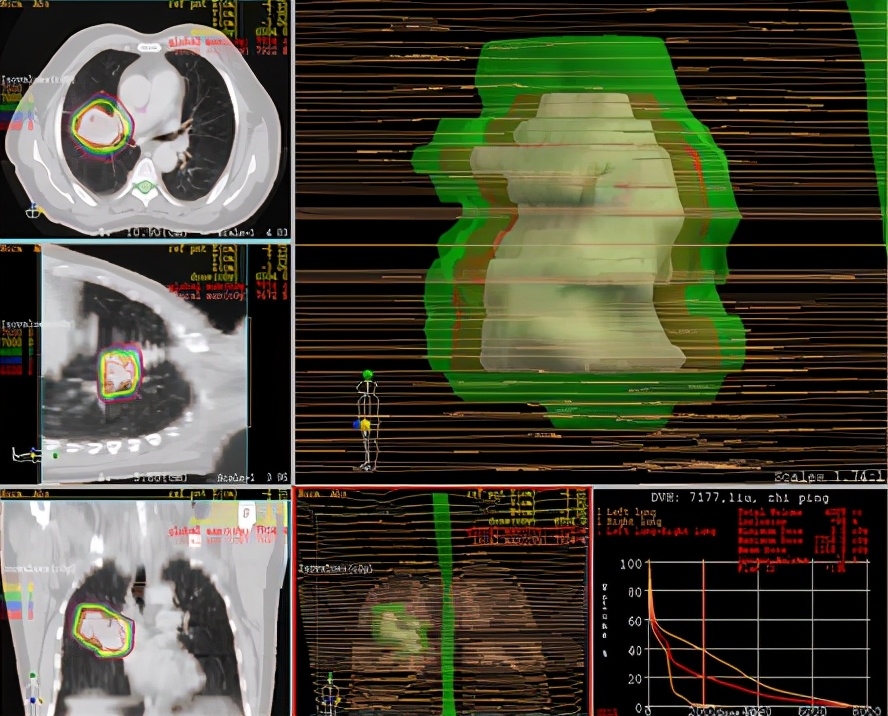

因二次全麻下气管插管出现哮喘无法手术,于2007年5月30至2007年6月28日进行局部放射治疗,同时给予对症支持治疗。照射剂量PTV(肿瘤外5mm)66GY/22f/30d;GTV(肿瘤边缘)70GY/22f/30d;GTV1(肿瘤内部)77GY/22f/30d;治疗期间,咳嗽缓解、无咯血,血常规 基本正常 范围,按计划完成治疗。